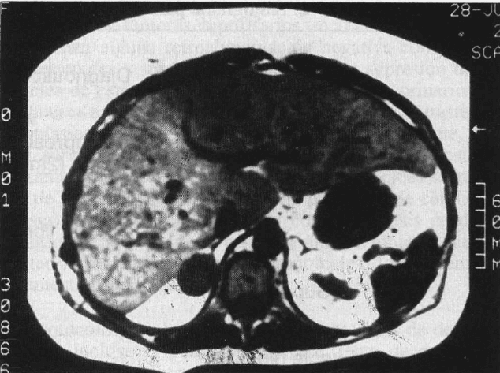

Cuando el síndrome de Cushing es debido a un adenoma adrenal autónomamente funcional, se observará una masa unilateral en la CT. El resto de la glándula ipsolateral no incluida y la contralateral, aparecerán normales o atróficas (Fig. 5). En la Fig. 6 se’ muestra la glándula adrenal extirpada con el tumor observado en la CT de la Fig. 5. Los adenomas tienden a ser esféricos y pequeños, mientras que los carcinomas son más grandes de 5 cm y tienen una forma irregular o lobular.

| Fig. 5. Tomografía axial que señala la presencia de un adenoma de la suprarrenal izquierda. |